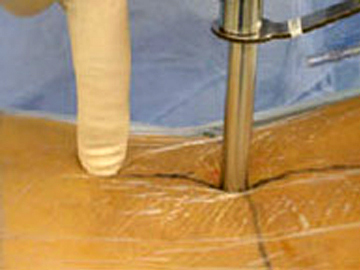

我院才用内窥视镜下椎管扩大术在极细的操作管当中完成减压术,给神经“松绑”。

此项技术是当今世界脊柱外科最先端的治疗手术方法之一。在极底的侵袭组织的情况下可完成椎间管扩大,最低程度对患者身体减轻负担,是一项最快捷,安全的治疗方法之一。

我院还对此项技术又进行改进以往18mm操作管现在仅有10mm。

可在全身麻醉的情况下只需2小时就可以完成手术。因为是低侵袭对组织的破坏很小,出血也很少因此对患者本人身体大大的减轻了负担,所以术后仅住两天便可出院。